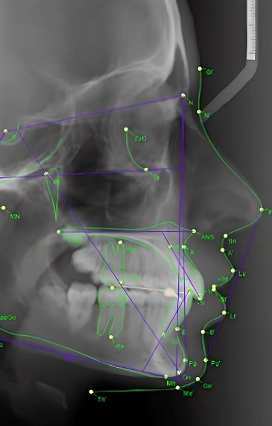

Цефалометрический анализ

Компьютерная оценка рентгеновского снимка головы в профиль.

Для чего: Определение соотношений челюстей, зубов и лицевого скелета.

Записаться на консультацию Записаться на цефалометрический анализ